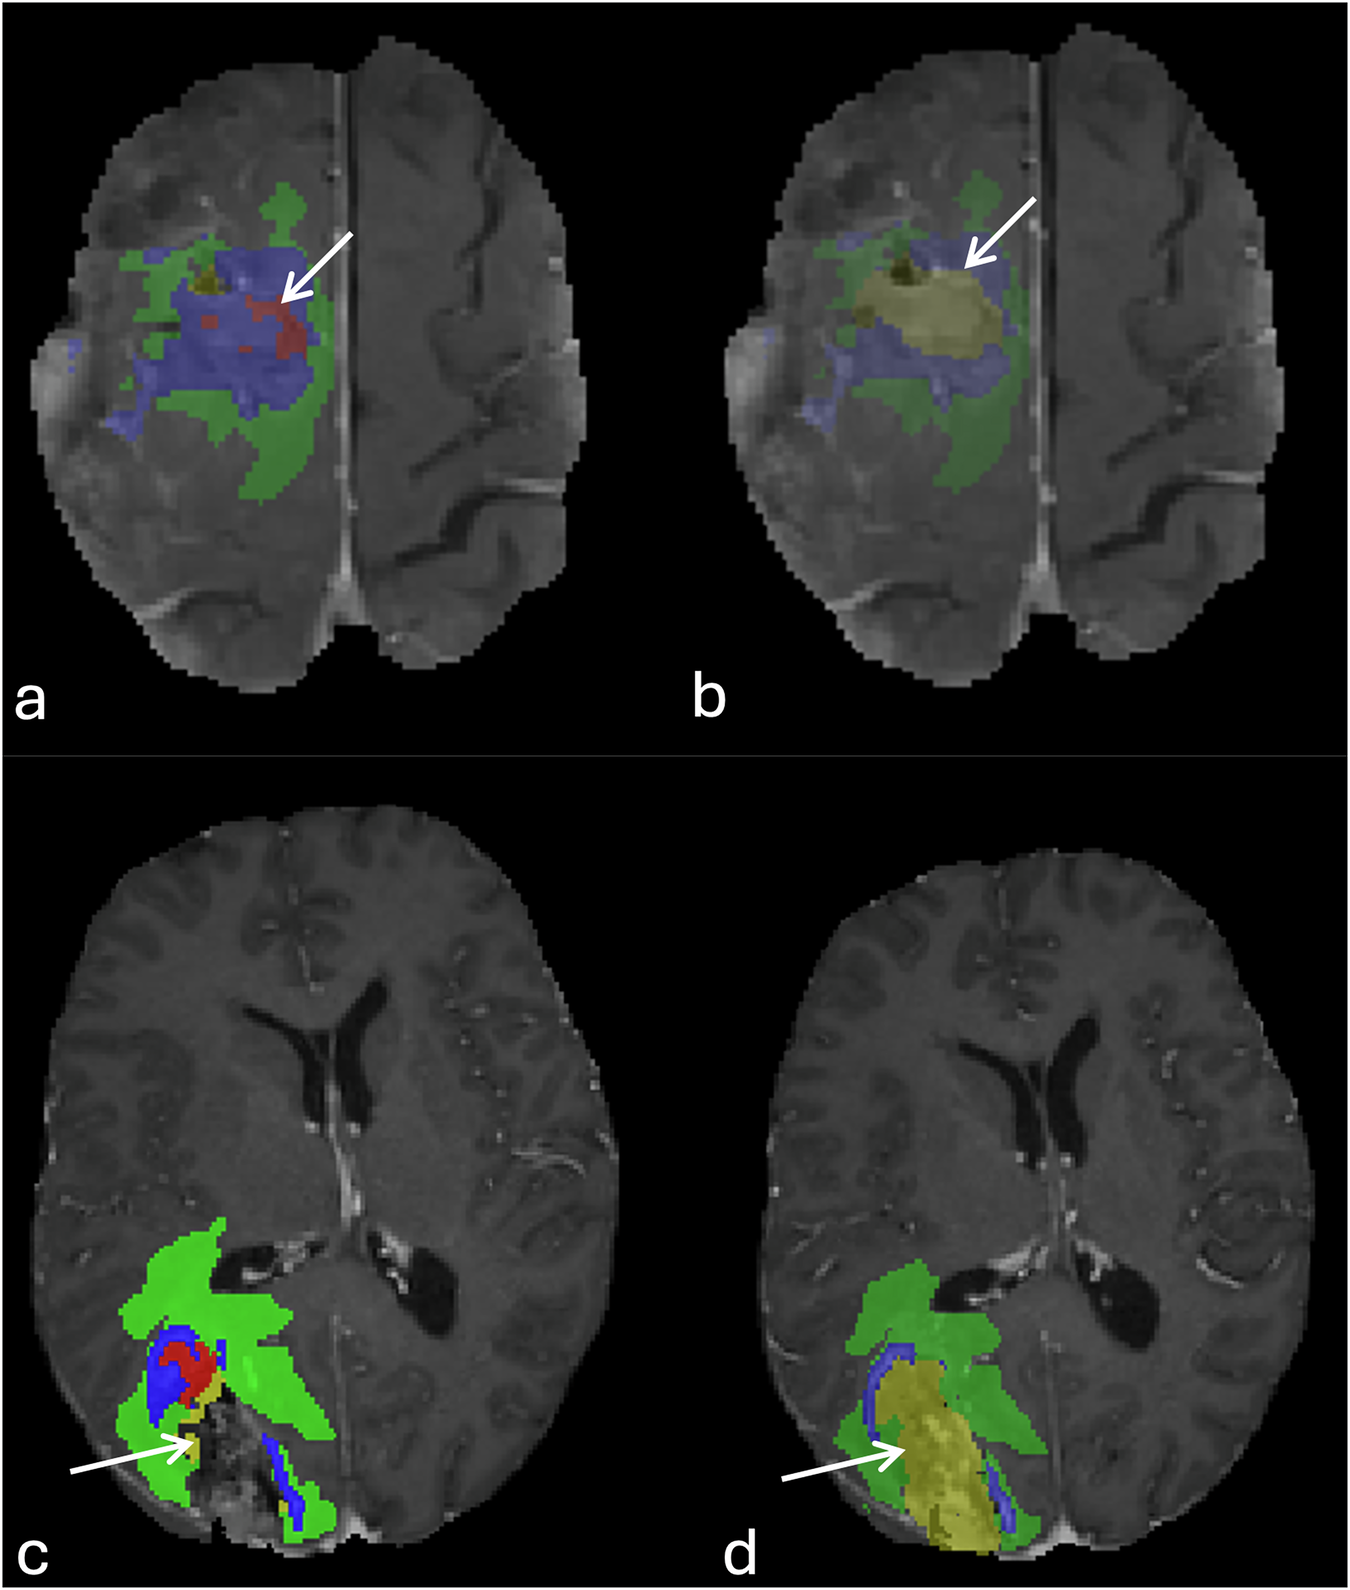

Fig. 4

Correction of a suboptimal automated segmentation. Panels (a) and (c) show an example of automated segmentation failure, where the model incompletely outlined the resection cavity. Panels (b) and (d) display the result after manual refinement to ensure the entire cavity was accurately labeled for the ground-truth dataset.